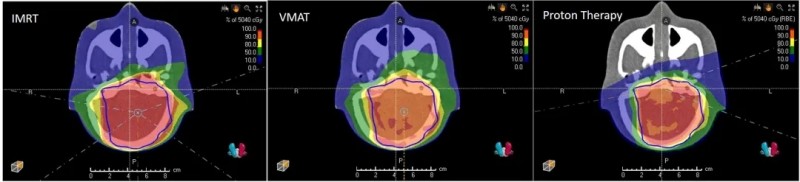

因此,儿童肿瘤放疗需尽可能减少健康组织暴露,而质子治疗被视为儿童癌症的首选放疗方式——它能在精准抗癌的同时,最大限度降低晚期放疗副作用,有效保护儿童免受智商下降、生长迟缓、发育障碍、继发性肿瘤等长期伤害。下图为传统放疗[调强放射治疗(IMRT)、容积调强放射治疗(VMAT)]与质子治疗(ProtonTherapy)的器官暴露剂量对比。

▲图源“frontiers”,版权归原作者所有,如无意中侵犯了知识产权,请联系我们删除